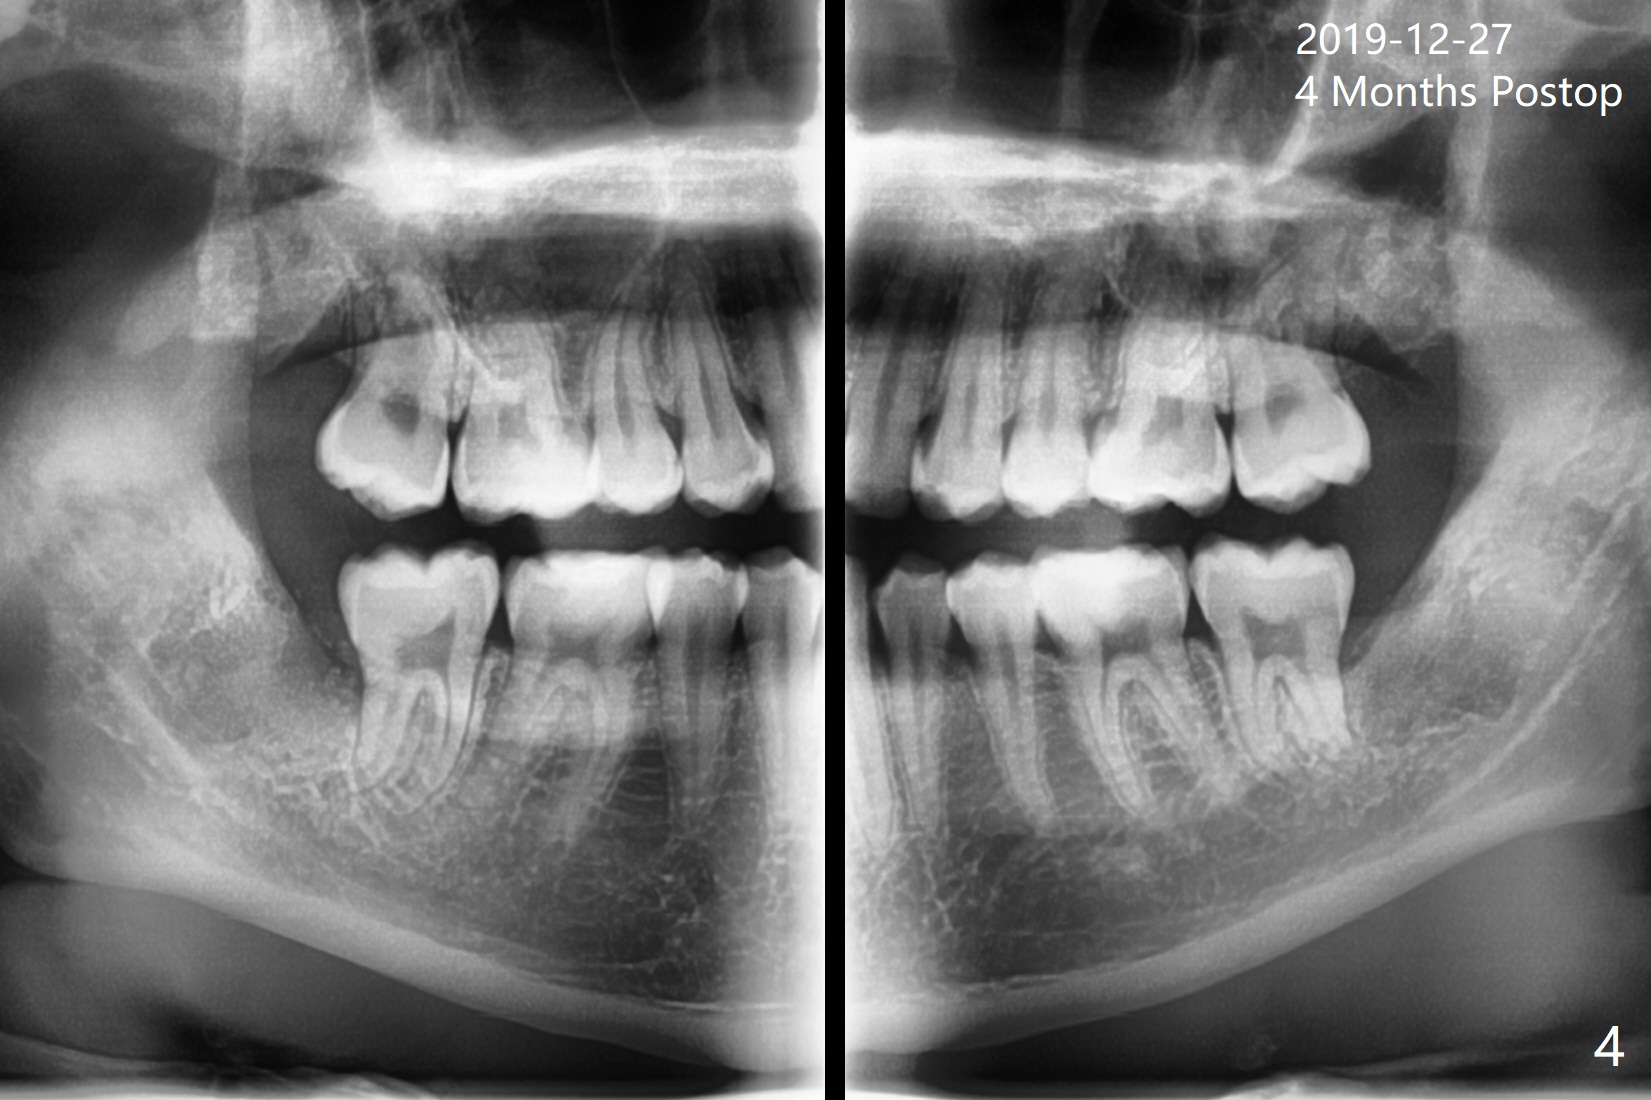

A 22-year-old man, asymptomatic, is going to have #1,16,17 and 32 extracted (Fig.1, fully bony impaction).  For the large lower sockets (actually Buccal Impaction), collagen plug (Fig.3 C) is placed in the inferior half, while Bone Cement (Bond Apatite from Augma (Fig.2,3 A)) and Osteogen plug (Fig.3 O) in the superior half at #32 and 17, respectively.  4-0 Chromic gut suture is used to close the wounds.  The four sockets heal (with increased bone density) 4 months postop (Fig.4).